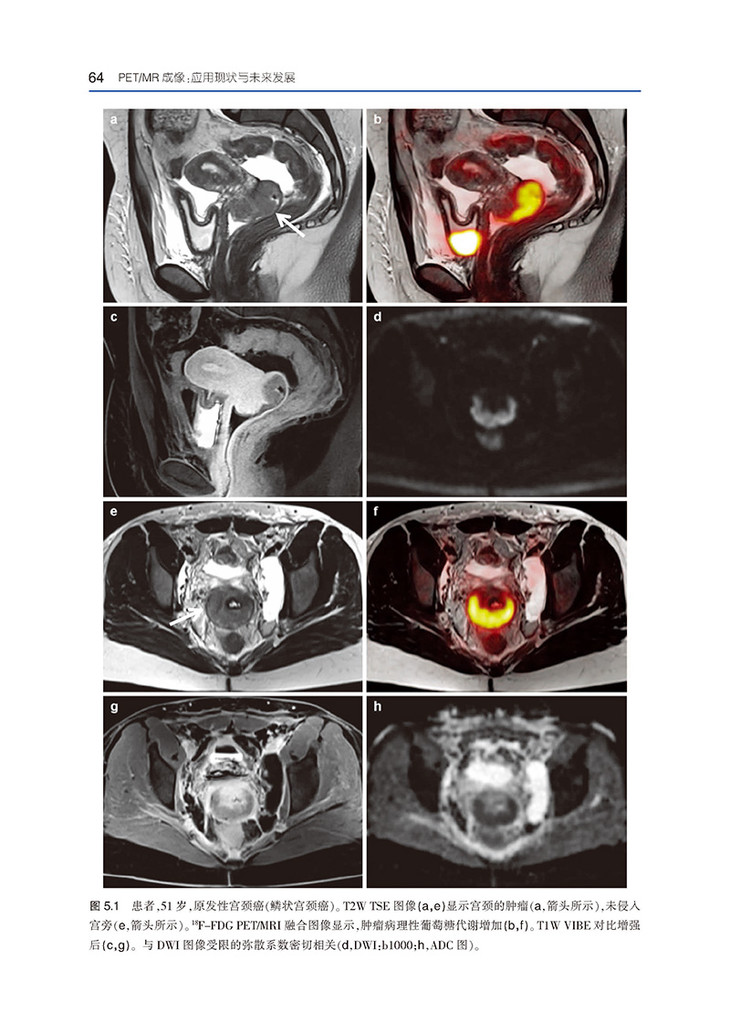

《PET/MR成像:应用现状与未来发展》共10章内容,详细阐述了PET/MRI在肿瘤、前列腺癌、女性盆腔肿瘤、乳腺癌、神经退行性疾病、心脏疾病、炎性疾病、儿科成像中的应用,包括操作技术、应用方法和发展前景。还介绍了PET/MR成像在监测接受靶向药物治疗的患者反应中的新兴作用,以及开发新示踪剂的进展。本书图文并茂,内容实用,可供核医学科、放射科及相关医护人员参考阅读。